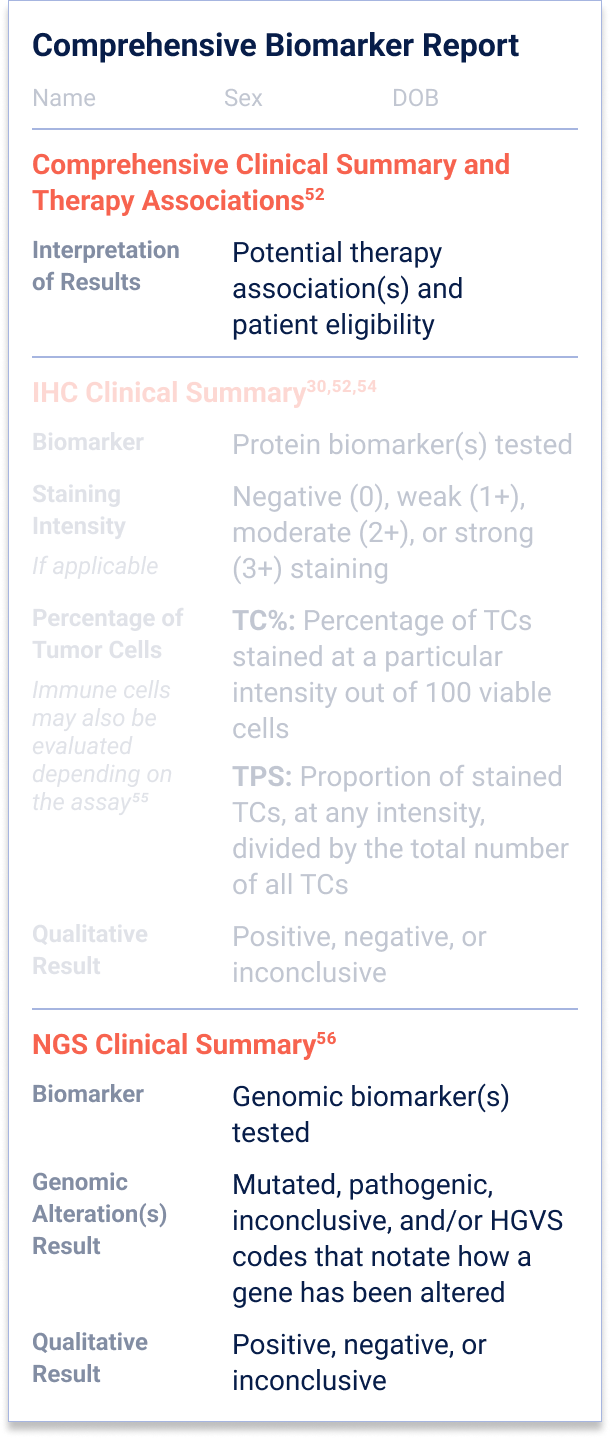

52. Penault-Llorca F, et al.

Virchows Arch. 2022;481(3):351-366.

54. Baskovich B, et al.

Arch Pathol Lab Med. 2024;148(10)1105-1109.

55. Mayo Clinic Laboratories. PD-L1 Testing by Immunohistochemistry. Accessed November 20, 2025.

https://news.mayocliniclabs.com/2022/08/22/pd-l1-testing-by-immunohistochemistry/.

56. Schmid S, et al.

ESMO Open. 2022;7(5):100570.